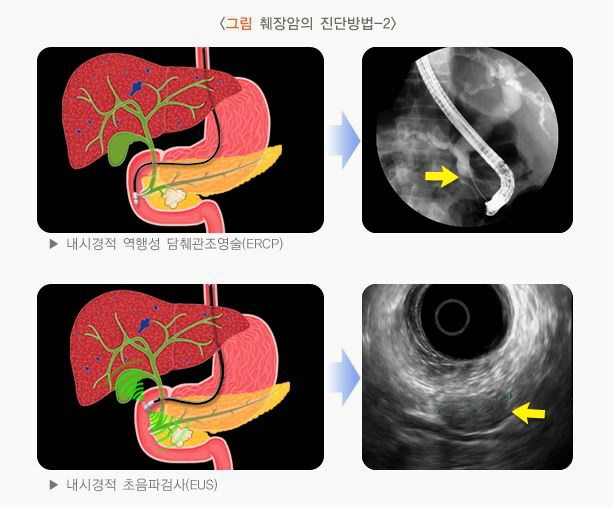

- 내시경 초음파(EUS), ERCP: 필요 시 시행

- 내시경 초음파(EUS), 조직검사